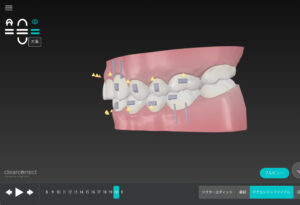

🔶アフター🔶

正面

右